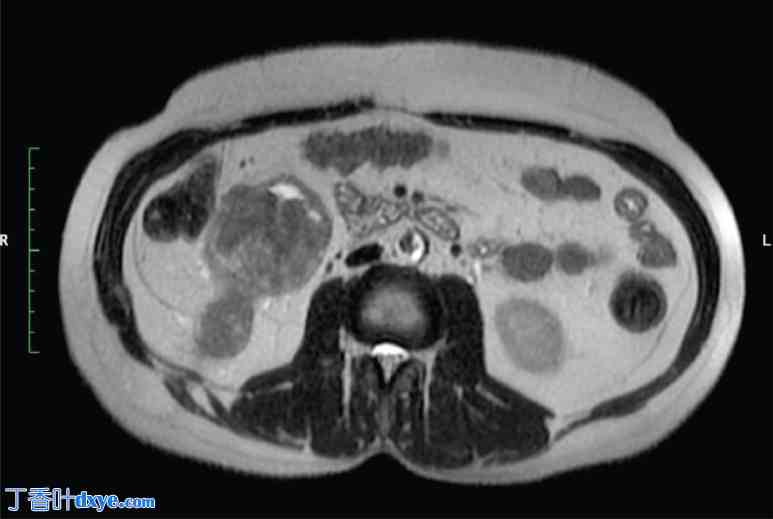

一位54岁男性患者,既往无其他疾病,因右侧腰痛就诊。非增强CT检查证实其肾盂内有鹿角状结石,未见可疑肿块。随后,患者接受了两次经皮肾镜取石术(PCNL),直至结石完全取出。术后3个月,患者持续出现右侧腰痛和偶发性血尿,遂转诊至院。进一步行增强CT和磁共振成像(MRI)检查,发现右肾内存在一强化病灶,从肾盂延伸至PCNL手术通道,并伴有腔静脉后、主动脉腔静脉和腔静脉前淋巴结肿大(图1-4)。CT引导下穿刺活检证实为高级别鳞状分化癌。血尿素氮为30 mg/dL,肌酐为1.2 mg/dL,钙为9.2 mg/dL,磷酸盐为3 mg/dL。尿细胞学检查发现发育不良细胞,二乙烯三胺五乙酸(DTPA)检查显示患侧肾脏肾小球滤过率降低至20 mL/min,未见其他部位转移。因此,患者接受了根治性肾切除术,同时整块切除了两个经皮肾镜取石术(PCNL)通道、受累皮肤和侧腹肌,并进行了基于模板的腹膜后淋巴结清扫术,随后进行了网片重建。术后恢复顺利。最终的组织病理学检查结果显示,肾脏大小为15 × 8 × 8 cm,输尿管长12 cm,以及两块分别包含下方PCNL通道的皮肤,大小分别为8 × 3.5 × 5 cm和5 × 2.5 × 2 cm。显微镜检查显示肿瘤从肾盂浸润,穿过肾周脂肪组织延伸至经皮肾镜取石术(PCNL)通道直至皮肤,组织学特征提示为2级鳞状细胞癌(SCC)。所有切缘均未见肿瘤残留,也未见淋巴血管或神经周围浸润的证据。此外,29个清扫的淋巴结均未见转移。患者接受了辅助放疗,照射范围包括肿瘤床和腹主动脉旁淋巴结区域,总剂量为50.4 Gy,分28次完成。此外,患者还接受了为期12周的化疗,每周一次,方案为紫杉醇80 mg/m²联合卡铂(AUC 2)。随访2年后,患者仍无复发。

图 3. 腹部 MRI 冠状位 T2 图像显示右肾周围的通道。

3.jpg